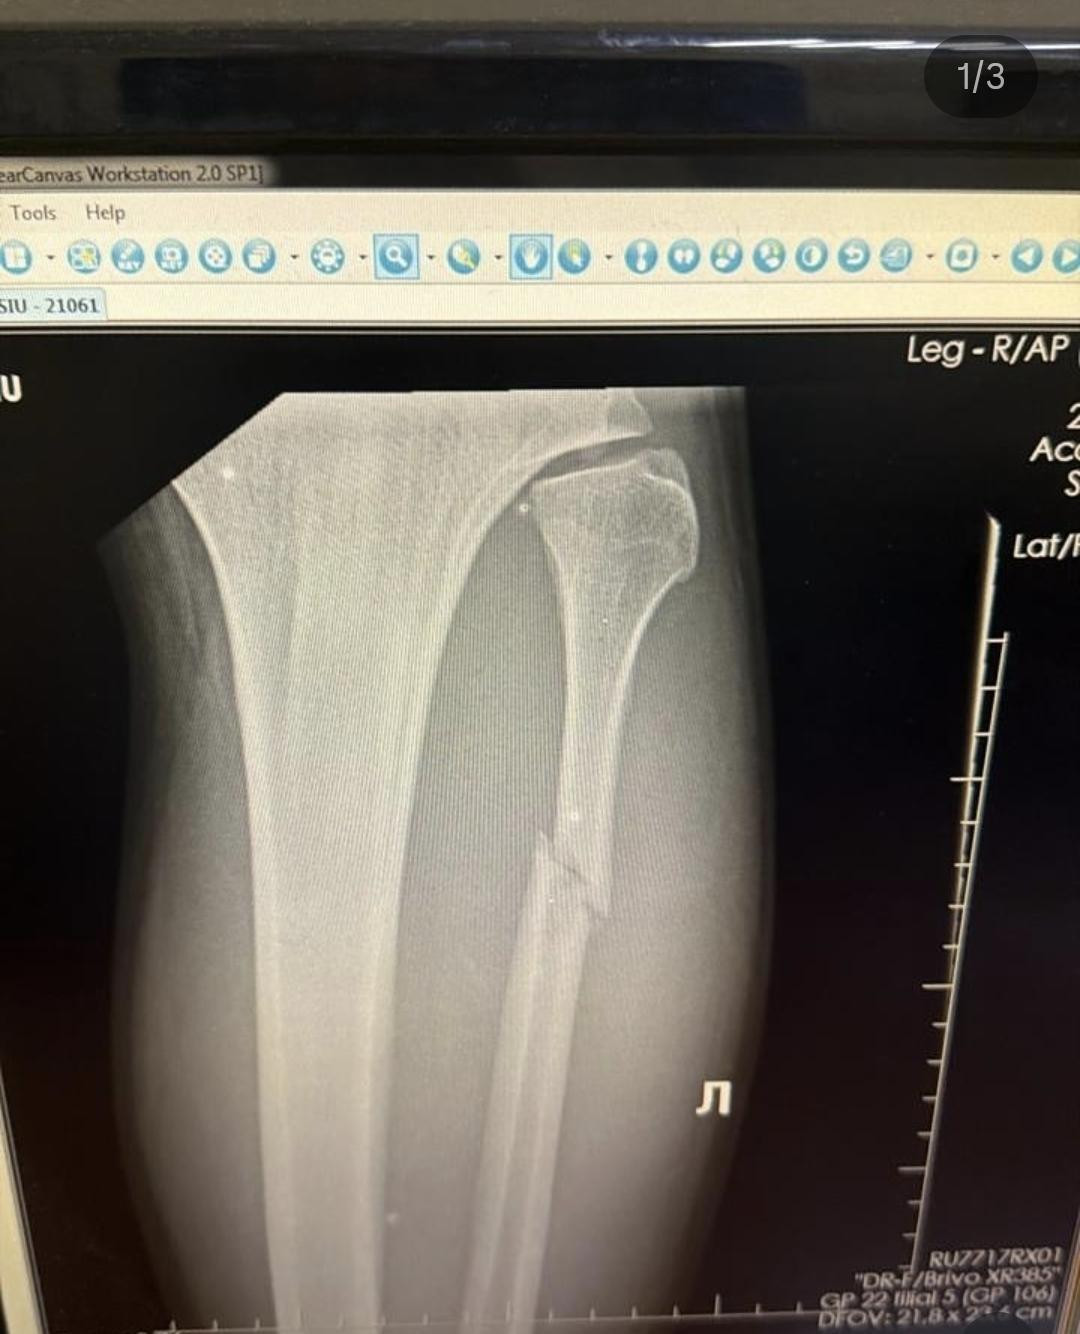

Nakon snažnog calf kicka, Walker je zadobio lom fibule u lijevoj nozi

Walker je u utorak otkrio da je slomio lijevu fibulu (lisnu kost) nakon što ga je Sutherland u ranoj fazi borbe pogodio snažnim udarcem u list (tzv. calf kick). Unatoč tome, 27-godišnji Brazilac je uspio srušiti protivnika na tlo i prisiliti ga na predaju.

Walkerova ozljeda

Screenshot/Valter Walker Instagram